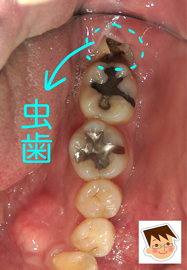

コラム「親知らずが歯茎の中で崩壊」の画像